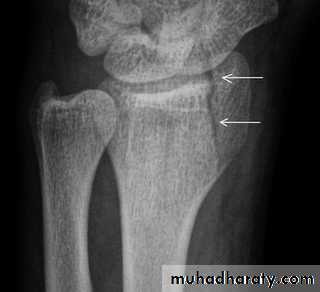

Radio-ulnar discrepancy.Radial styloid fracture

Caused by forced radial deviation of the wrist.the fracture line is extend laterally from the articular surface of the radius.Treatment: